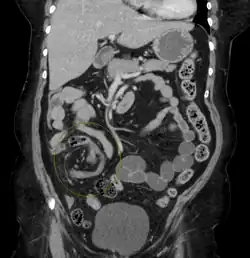

CT scan of a cecal volvulus